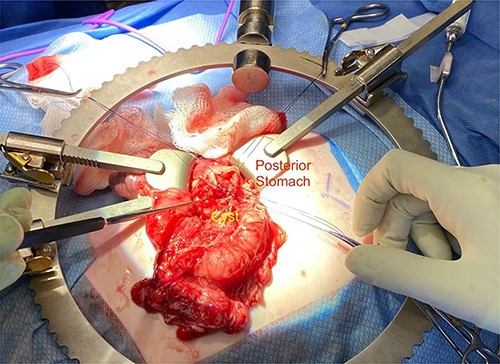

We noted that the patient had an annular pancreas; there was pancreatic tissue around D2 with no evidence of stenosis. There were dense adhesions between the posterior wall of the stomach and this mass, which was essentially embedded within the head of the pancreas and closely positioned but separate from the medial wall of D1 and posterior stomach. There was scarred inflammation extending along the transverse mesocolon, but no true fistula was seen (Fig. 2). There was no evidence of a connection to the pancreatic duct. An intraoperative ultrasound revealed a thick-walled cyst; the fluid in the cyst was of low density with areas of mucous debris dependently (Fig. 3).

Intraoperative image showing the duplication cyst in relation to surrounding organs, and the inflammatory tissue extending from the mass to the colon (at the tip of the forceps).